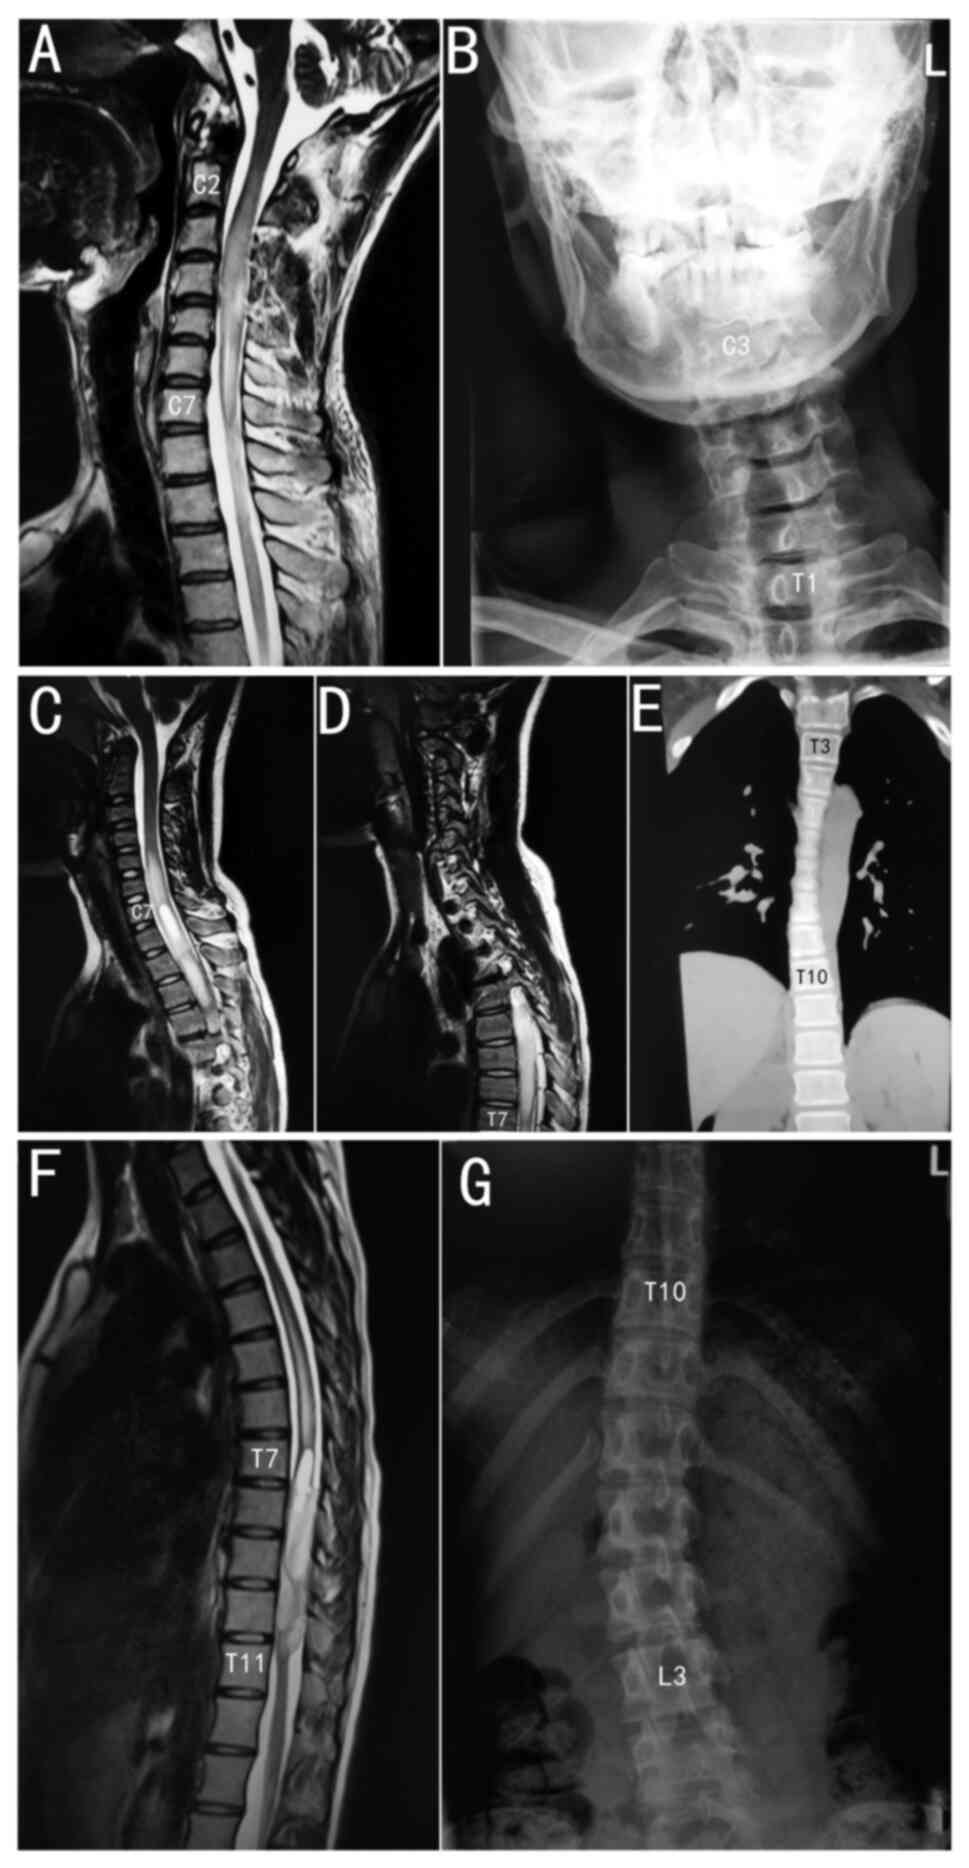

The details of the patients with scoliosis with

complete information are listed in Table III. The inferred tumour side was

highly consistent with the convex side of scoliosis. According to

classic anatomical studies, in early human embryos, the spinal cord

has the same length as the spine, and each spinal cord segment is

consistent with the corresponding vertebral bone. However, in the

process of growth, the growth rate of the spine is faster than that

of the spinal cord. Therefore, in adults, spinal cord sections do

not precisely correspond to the corresponding vertebral bones

(24). The corresponding rules are

listed in Table IV. The sagittal

position of the astrocytoma and scoliosis end vertebra follow the

same rules. Three typical cases are shown in Fig. 1: A C2 to C7 segment tumour caused C3

to T1 segment scoliosis, a C7 to T7 segment tumour caused T3 to T10

segment scoliosis and a T7 to T11 segment tumour caused T10 to L3

segment scoliosis. Unlike idiopathic scoliosis, the apical

vertebrae were generally in the middle of the scoliosis, and the

apical vertebrae were more caudal to this scoliosis type. In some

cases, the apical vertebra was the caudal end vertebra.

Morphologically, the vertebral bodies of idiopathic scoliosis line

up similarly to a ‘c’ shape, whereas the vertebral bodies of

astrocytoma-induced scoliosis in the present study lined up

similarly to an ‘L’ shape with a larger angle. The morphology of

this scoliosis type in the cervical, thoracic and lumbar spine is

shown in Fig. 2.